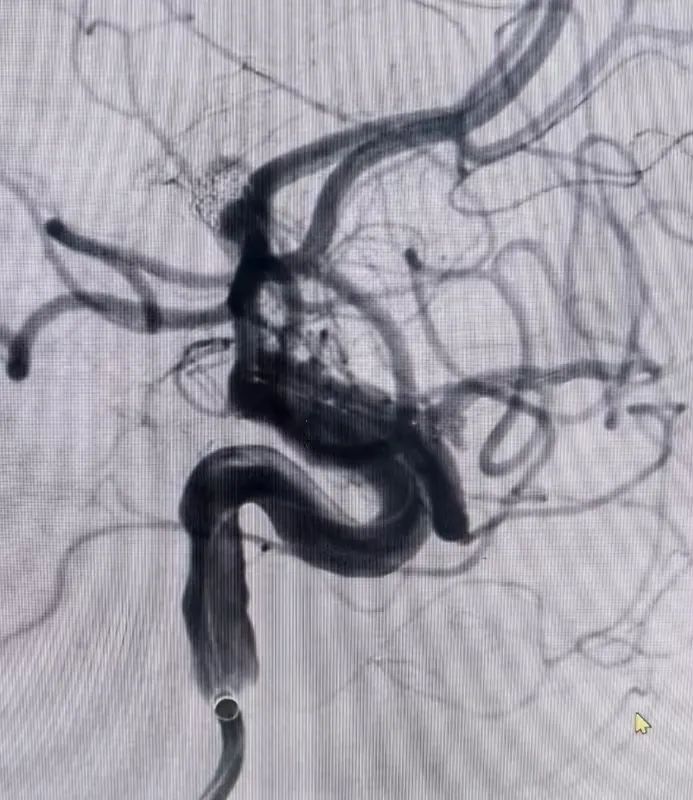

硬脑膜动静脉瘘患者同样在个性化方案中重获新生。患者因反复头晕,在外院怀疑静脉畸形,来到东方总院后,脑血管造影明确为硬脑膜动静脉瘘。通过详细的沟通,家属选择介入栓塞,吴全主任团队采用介入打胶栓塞的治疗方式,精准地堵住异常血管,一次性完全栓塞,术后患者头晕症状消失,生活质量大幅提升。